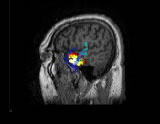

多模式神經(jīng)(腦)影像、腦活動(dòng)源精確定位、2D/3D影像,CURRY是功能非常強(qiáng)大的電磁溯源分析定位和可視化工具,該軟件在世界上處于最領(lǐng)先地位,推動(dòng)了神經(jīng)(腦)影像的飛速發(fā)展。

CURRY軟件包含多種功能,可以充分整合各種影像數(shù)據(jù)格式(EEG、MEG、MRI、fMRI、CT等)。通過將腦電活動(dòng)與各種自發(fā)或功能影像數(shù)據(jù)的有機(jī)融合,CURRY為腦活動(dòng)源的定位和分析提供了強(qiáng)有力的工具。CURRY可以利用MR和CT等得到的真實(shí)解剖結(jié)構(gòu)影像,建立每個(gè)被試的顱骨和腦的3D模型(該模型對探明神經(jīng)活動(dòng)的發(fā)生源至關(guān)重要)。CURRY還可以將功能影像(如fMRI)和EEG、MEG的溯源重建進(jìn)行比較,以增強(qiáng)結(jié)果的準(zhǔn)確性。 CURRY可以在PC機(jī)、工作站、Laptops等運(yùn)行,不僅可以用于研究工作(如腦的功能成像),而且,其強(qiáng)大的功能和先進(jìn)性使其具有了更為廣泛的應(yīng)用(如臨床、功能評估等)。

結(jié)果的清晰可視化:

CURRY可以清晰地呈現(xiàn)具有高分辨率的各種影像及3D 重建結(jié)果(皮層、顱骨、頭皮、皮層斷層)。同時(shí),可以觀察3D影像結(jié)果的動(dòng)態(tài)變化(如3D Movie),具有很高的時(shí)間分辨率,也可以進(jìn)行體積測量。